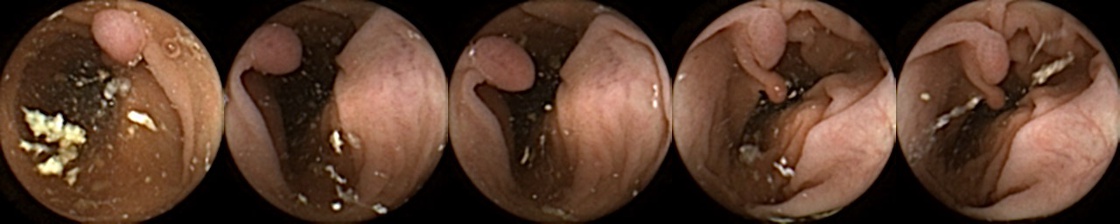

Similarly, we consider examples for the MIV model based on SimCLR pretraining using the pretrained ConvNext backbone in Figure 4. The model has a test accuracy of 86.26% for DBA L1 with 2 heads. Here we note again a similar trend by looking at the True Positive and False Negative examples as observed before, where a significant difference in the query image when compared with the target images can lead to a failure to identify the same polyp images in the five examples. A look at the False Positive examples affirms that the task remains challenging, as evidenced by the model’s occasional misclassifications in ambiguous cases.

Figure 4: True Positives (Pred = true, Label = true), False Negatives (Pred = false, Label = true), False Positives (Pred = true, Label = false),True Negatives (Pred = false, Label = false) for the DBA L1(h=2) model applying SimCLR using the ConvNeXt backbone. In each row, the leftmost image is the query and the 4 images to the right of each query are the target images.